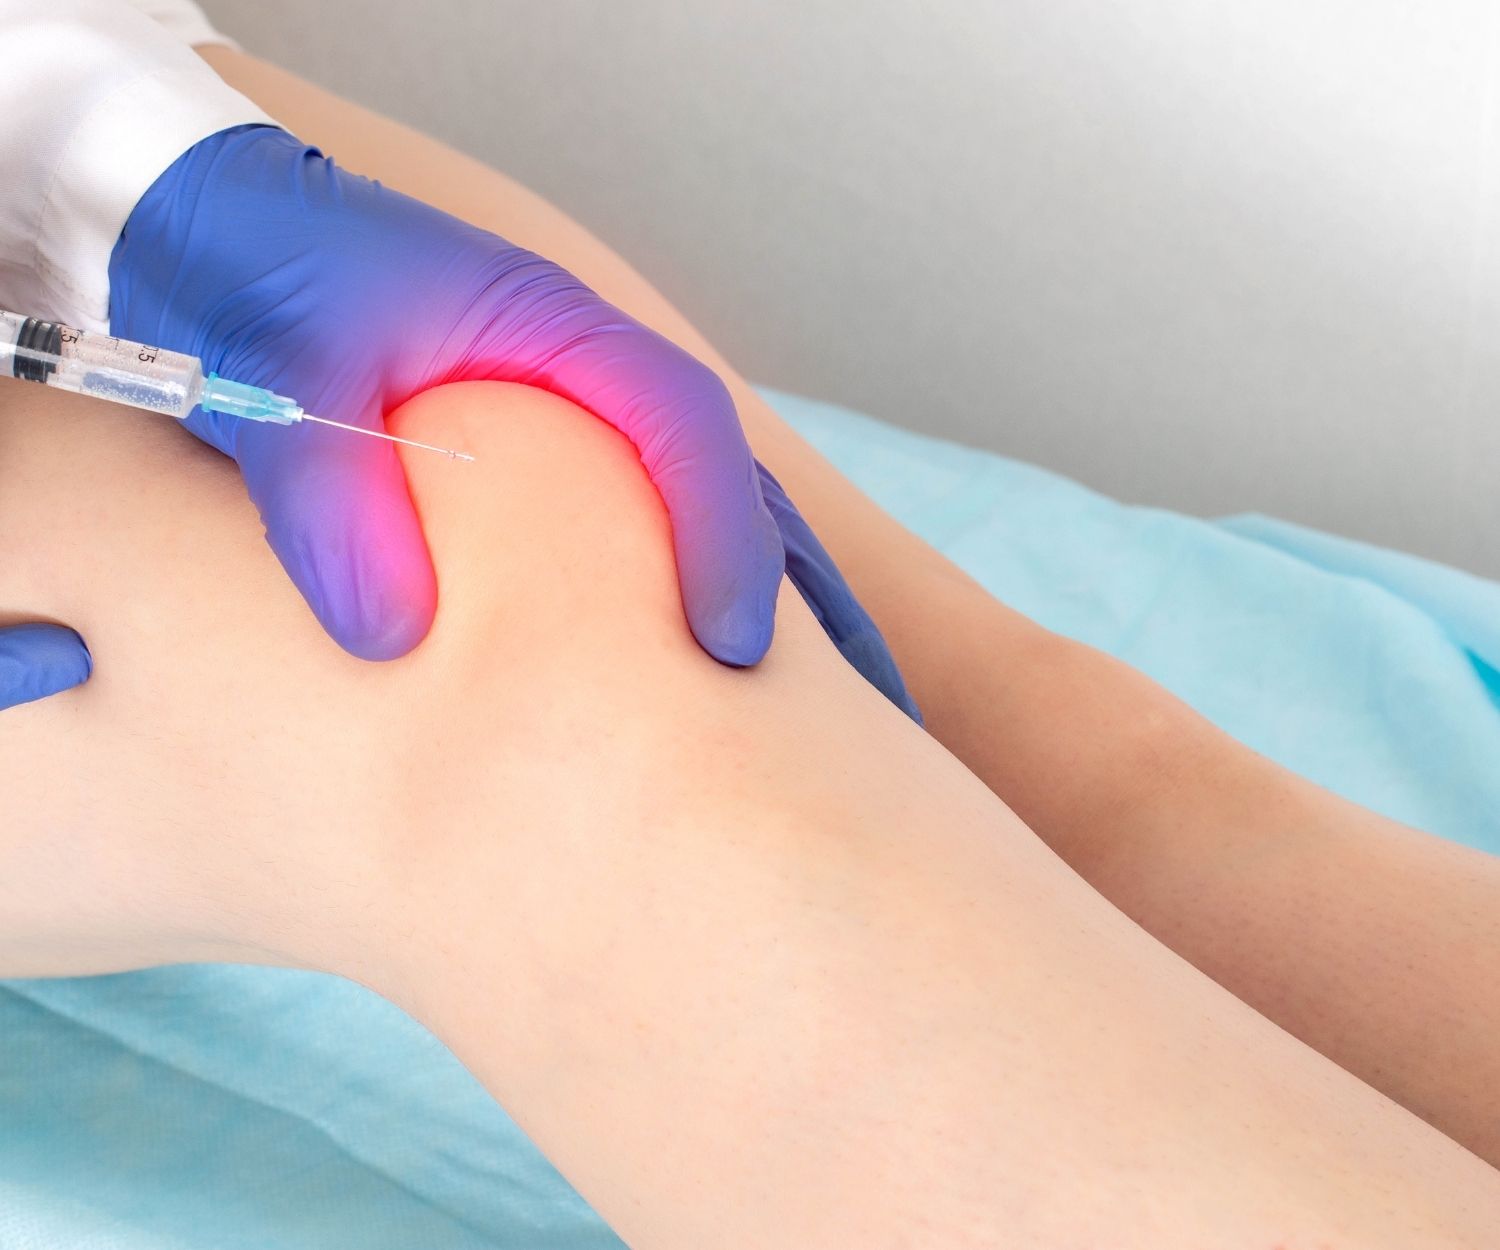

PRO-HEALTH INJECTIONS

We use a variety of healthy joint injections for different case presentations, patients, and levels of severity to help expedite the healing process. We offer a 1% lidocaine or marcaine & 99% saline injection for relatively healthy, but inflamed joints. We use Platelet-Rich Plasma (PRP) injections for anything that needs a new healing response. We offer human cellular tissue injections for anyone who needs more cushion and lubrication to help damaged joints and soft tissue heal. We will NEVER use a cortisone injection as it promotes cell death and fast tracks you to a surgery!